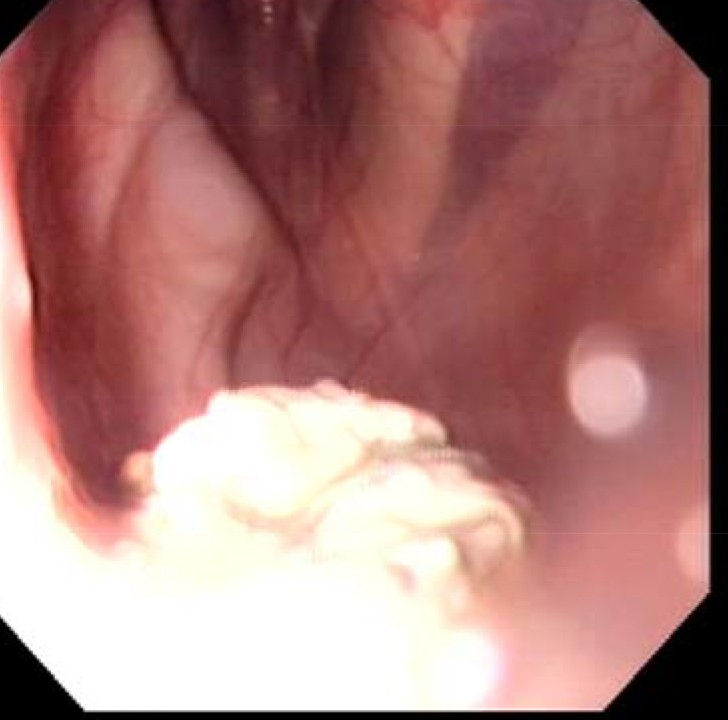

Nous ça donnait heureusement ça au niveau de la poche gauche (conduit de la plaque)

Photo de mauvaise qualité car prise depuis le telf.